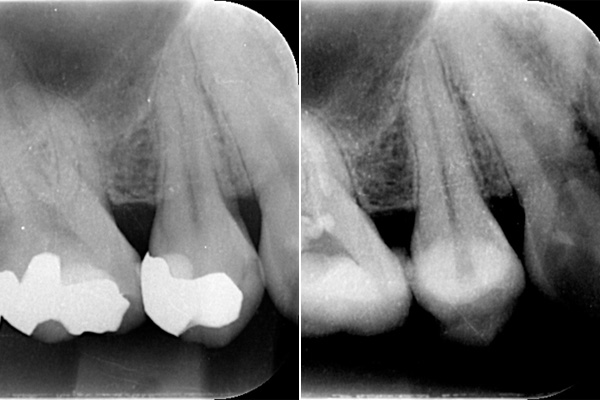

根の先端に膿が溜まっています。

根の中の白い縦の線がなくなっています。これは、中に詰まっていた、防腐剤を取り除いた証拠になります。取り除いてから、根の中をしっかり清掃していきます。

清掃が終わり、患者様も違和感がなくなったということで、防腐剤を再び詰めていきました。最初に入っていたものと比較して緊密に太く入っているのがわかります。

6ヶ月後。根の先端に溜まっていた膿(黒い影)がなくなっています。なくなったことが確認できてから、かぶせ物をかぶせていきます。

根の中に入っていた防腐剤を取り除いた時の写真です。感染物質が付着して黒くなっているのがわかります。

また、防腐剤をとりのぞけても、その防腐剤を歯の根のなかにくっつける素材が残っていますので、それもしっかり取り除きます。

目ではなかなか全てを見ることができないので、右の写真の様にマイクロスコープをもちいて拡大してみていきます。

こちらは根の途中までしか防腐剤がはいってませんでした。患者様が違和感を訴えたため、治療を行いました。防腐剤を取り除き、根の中を清掃し、根の先端までしっかり防腐剤をいれました。